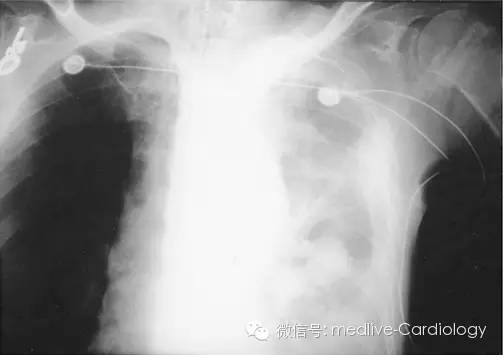

如果主动脉夹层破裂,血液会外渗到同侧胸膜腔中,导致血胸形成。如下图所示,大量血胸在胸片上会表现为同侧全肺野透过度减低。